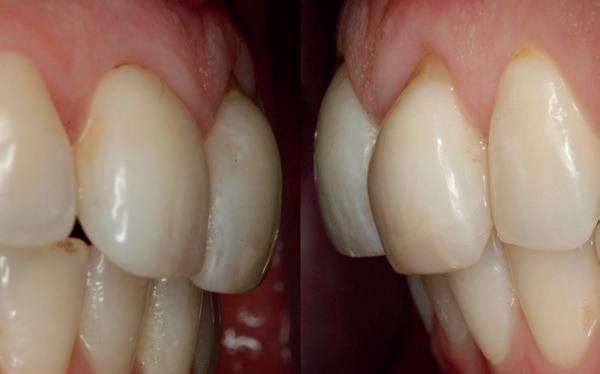

De flap en graft worden met poly-propelene 6.0 hechtingen gefixeerd. De tijdelijke reconstructie wordt herplaatst (foto 17-20).

Na 4-6 weken kan het aangebrachte healing abutment worden vervangen door een tijdelijk abutment. Deze wordt aan de kunststof reconstructie verbonden om zo de gingiva ter plaatse van de 22 te vormen. Zo lijkt het of er geen implantaat maar nog steeds een wortel aanwezig is, wat het esthetisch eindresultaat ten goede zal komen (foto 21-23). Vanaf 4-6 maanden ziet het weefsel er gezond uit. Nu kan met de uiteindelijke restauratiefase worden gestart (foto 24 en 25).

Er wordt een afdruk of een intra-orale scan genomen van de situatie met tijdelijke voorzieningen en de geprepareerde situatie. Ook mag een portretfoto en mondfoto niet ontbreken. Al deze informatie gaat naar het laboratorium zodat de onderstucturen van de restauraties gemaakt kunnen worden (foto 26).

De vier restauraties worden in samenspraak met de ceramist en de patiënt gecustomized. Op dit moment kunnen er nog details worden aangepast om zo het mooiste eindresultaat te behalen.

Bij de evaluatie van deze casus blijkt dat het herstellen van de processen alveolaris ter plaatse van de 22 is gerealiseerd en dat de gingiva qua positie en volume rond de 22 en 23 is verbeterd. Het implantaat is goed ge-osseointegreerd en de gingiva rond het implantaat heeft een natuurlijke vormgeving gekregen. De kronen zijn met moderne technologie en esthetisch hoogwaardig vervaardigd door het Oral Design Center Holland. Met dank aan Eric van der Winden.

De dentale mediaanlijn is rechtop gezet, maar staat niet helemaal gelijk met de faciale mediaan. Echter, mevrouw is functioneel en esthetisch naar tevredenheid afbehandeld (foto 27-30).